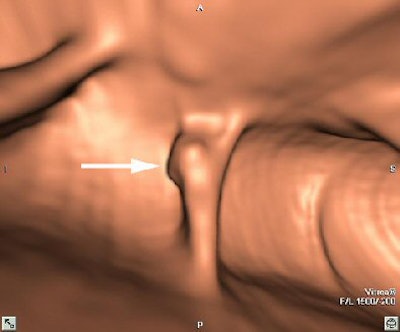

| Coronal VC image confirms the presence of the polyp (arrow) within descending colon. Image courtesy of Dr. Riccardo Iannaccone. |

As for study limitations, the cohort remains relatively small, and the observers "have vast experience using primary 2D," Iannaccone said. Readers with less experience might have different results.

"CTC without cathartic preparation compares favorably with colonoscopy for detection of polyps 8 mm in diameter or larger, even in asymptomatic patients at average risk for colorectal cancer," Iannaccone concluded. "But certainly a larger cohort must be studied in order to confirm such promising results."